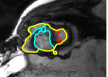

The problem above is a generalization of Horn & Schunck optical flow. Note that solving for the Horn & Schunck optical flow within each region separately does not lead to motions such that at the interface, they have equal normal components (see Figure 1), whereas the solution of (5) to be presented in subsequent sections does. Note that computing Horn & Schunck optical flow in each region requires boundary conditions (and typically they are chosen to be Neumann boundary conditions: and on ). Note that replacing these boundary conditions with the boundary constraint (6) does not specify a unique solution. Also, while Horn & Schunck optical flow computed on the whole domain naturally gives a globally smooth motion, which by default satisfies matching normals at the interface, this is not natural for the ventricles / myocardium, where different motions exist in the regions (see Figure 2), and the motions should not be smoothed across the regions.

![]() |

| image + boundary | global optical flow | our method | our method (motion decomp.) |